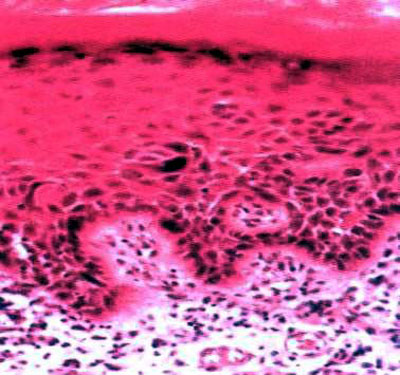

500)this.style.width=500;" border=0> 过度不全角化